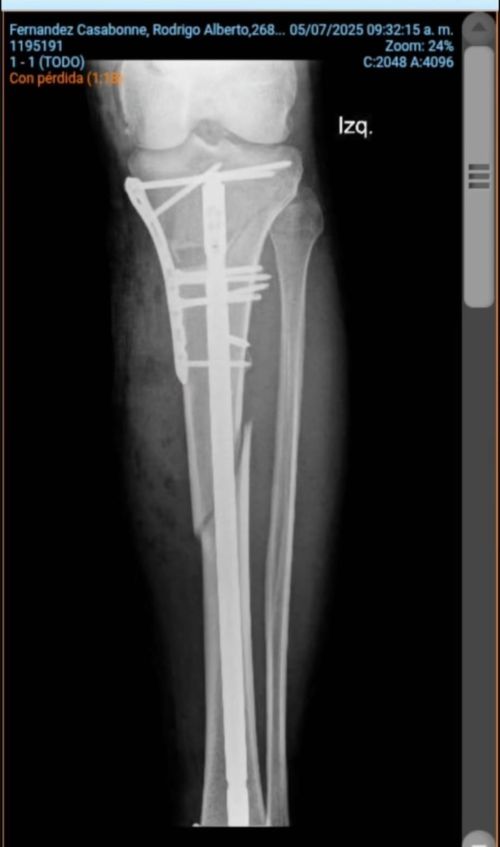

Rodrigo Alberto Fernández Casabonne

El piloto Fernández también expuso esta situación con un contundente video. “Así esta mi pierna hace un mes y medio. Tuve una fractura en una carrera de motocross, tuve una cirugía donde me pusieron un clavo intramedular mas una placa. Algunos habrán visto que puse la moto a la venta y el motivo es que no estoy encontrando respuesta de la cobertura sobre esta infección, me dicen que pasados los 3 meses no cubren.”